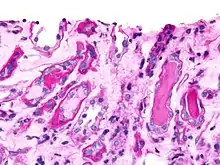

Histopathology

A bone marrow biopsy is usually performed to estimate the percentage of bone marrow occupied by plasma cells. This percentage is used in the diagnostic criteria for myeloma. Immunohistochemistry (staining particular cell types using antibodies against surface proteins) can detect plasma cells that express immunoglobulin in the cytoplasm and occasionally on the cell surface; myeloma cells are often CD56, CD38, CD138, and CD319 positive and CD19, CD20, and CD45 negative.[20] Flow cytometry is often used to establish the clonal nature of the plasma cells, which will generally express only kappa or lambda light chain. Cytogenetics may also be performed in myeloma for prognostic purposes, including a myeloma-specific fluorescent in situ hybridization and virtual karyotype.

The plasma cells seen in multiple myeloma have several possible morphologies. First, they could have the appearance of a normal plasma cell, a large cell two or three times the size of a peripheral lymphocyte. Because they are actively producing antibodies, the Golgi apparatus typically produces a light-colored area adjacent to the nucleus, called a perinuclear halo. The single nucleus (with inside a single nucleolus with vesicular nuclear chromatin) is eccentric, displaced by an abundant cytoplasm. Other common morphologies seen, but which are not usual in normal plasma cells, include:

• Bizarre cells, which are multinucleated

• Mott cells, containing multiple clustered cytoplasmic droplets or other inclusions (sometimes confused with Auer rods, commonly seen in myeloid blasts)

• Flame cells, having a fiery red cytoplasm[65][66]